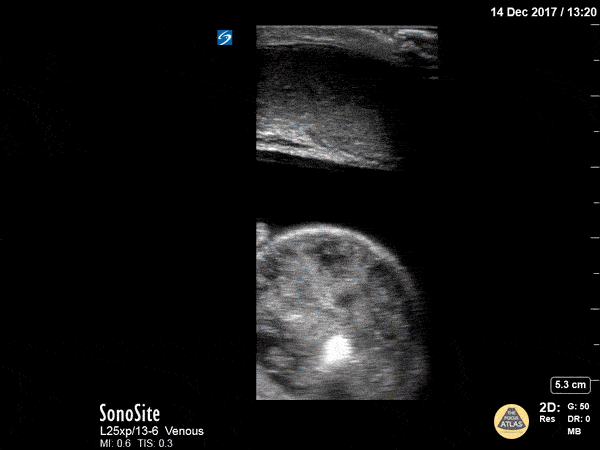

Bowel-GI - Strangulated Inguinal Hernia

60 year old male presents with pelvic and scrotal pain with vomiting x 1 hour. Physical exam significant for an edematous, erythematous, tender scrotum. Bedside ultrasonography revealed bowel peristalsis and marked scrotal edema (anechoic stripe) visible throughout the scrotum with several loops of bowel within the scrotum. IV established for analgesia and nausea control, and general surgery was consulted. The surgeon requested a CT even though there was good certainty of a strangulated hernia, for operative planning purposes. Patient went to the OR the same day and made full recovery. Pieter Ver Steeg, PA-C